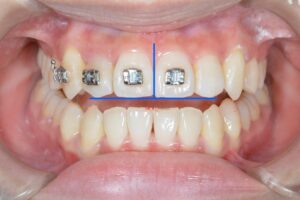

何が変わったのか分かりづらいので、こちらもご覧ください!

青が追加治療前の状態、白が追加治療後の状態を表しています。

右上2番目の歯を前に出す動きや、下の歯を全体的に寄せる動き、分かりづらいですが上の前歯の傾きを直す動きもしっかり組み込まれています。

ちなみに、11枚のアライナーのうち最後の3枚はオーバーコレクションステージと言って、歯を並べるための移動ではなく、残ってしまったわずかな隙間をキュッと寄せるためのアライナーとなっています。